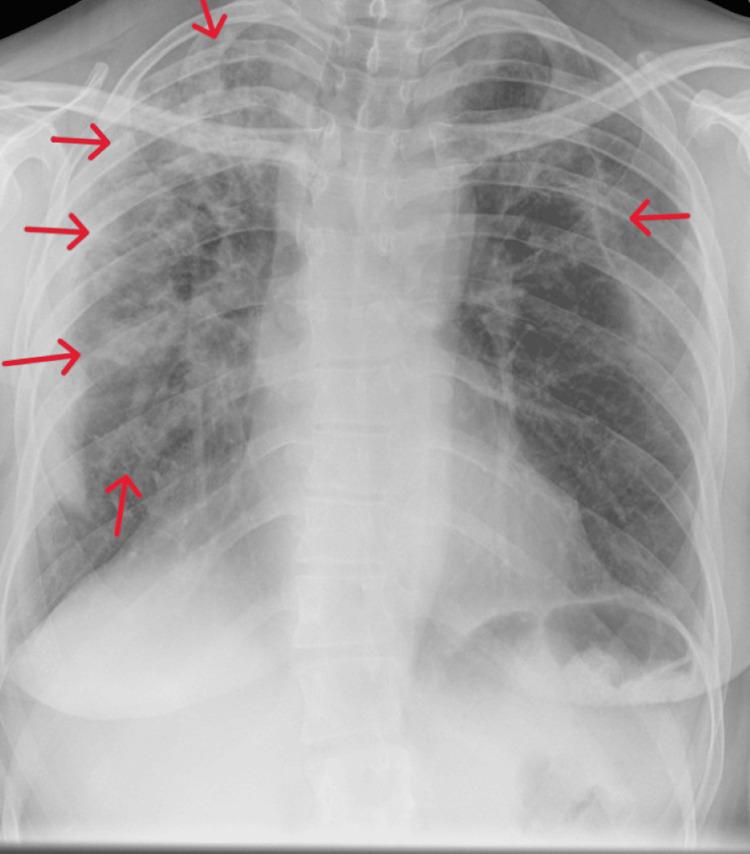

Eosinophilic pneumonia is a rare condition characterized by the infiltration of eosinophils in the lungs. We present a case of eosinophilic pneumonia in a 51-year-old British Caucasian female with a history of lichen sclerosus, deranged liver function tests, and a family history of atopy. The patient presented with fever, shortness of breath, lethargy, dry cough, and weight loss over a three-month period. Initial treatment with antibiotics did not yield improvement, and further investigations revealed marked eosinophilia on blood count. Bronchoscopy and biopsies confirmed the diagnosis of eosinophilic pneumonia, and the patient responded well to a tapering dose of prednisolone. This study highlights the importance of considering eosinophilic pneumonia in patients with unexplained respiratory symptoms and eosinophilia and emphasizes the role of bronchoscopy in establishing a definitive diagnosis.

嗜酸性粒细胞性肺炎是一种罕见疾病,其特征为嗜酸性粒细胞在肺部浸润。我们报告一例51岁英国白种女性嗜酸性粒细胞性肺炎病例,该患者有硬化性苔藓病史、肝功能检查异常以及特应性家族史。患者在三个月内出现发热、气短、乏力、干咳和体重减轻。最初使用抗生素治疗未见改善,进一步检查发现血常规显示明显嗜酸性粒细胞增多。支气管镜检查和活检确诊为嗜酸性粒细胞性肺炎,患者对逐渐减量的泼尼松龙治疗反应良好。本研究强调了在有不明原因呼吸道症状和嗜酸性粒细胞增多的患者中考虑嗜酸性粒细胞性肺炎的重要性,并强调了支气管镜检查在确立明确诊断中的作用。